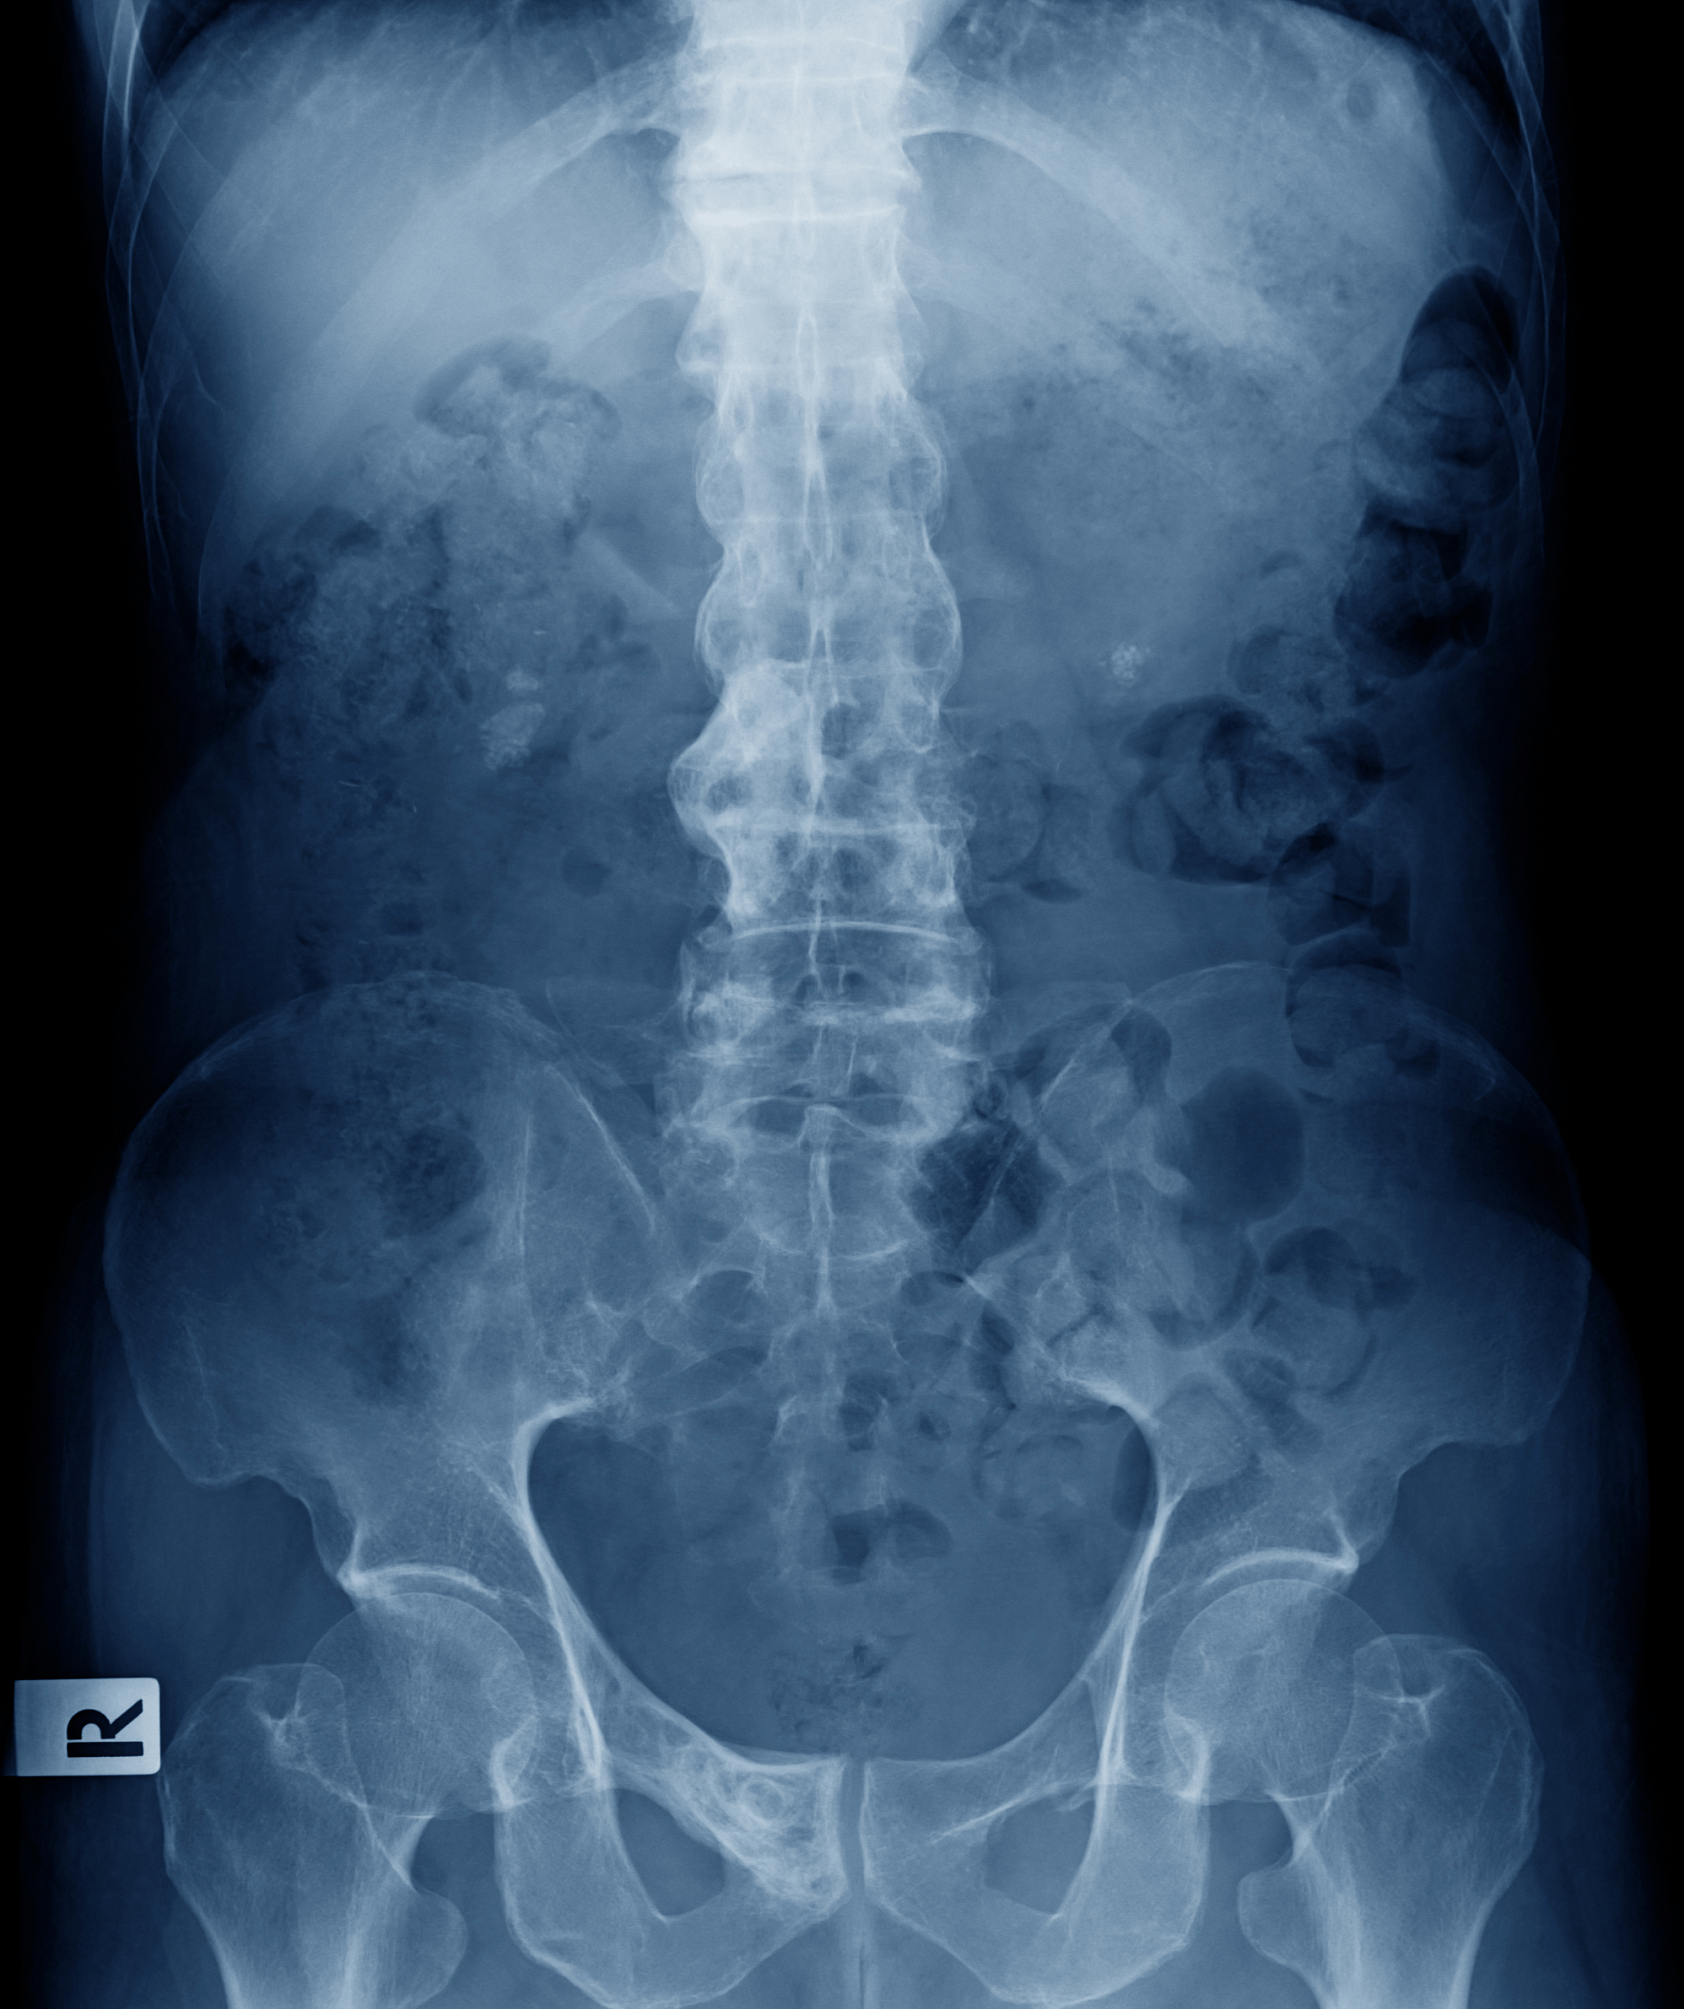

蘓荣医师特别强调说:强直性脊柱炎一旦到了晚期阶段,会出现关节融合,伴有脊柱关节畸形出现驼背、脊柱活动功能消失。一旦到了晚期,一般只能达到减轻疼痛的效果。药物治疗效果往往不佳。“工作劳累后,年轻人偶有腰背酸痛是普遍的症状,但如果出现超过3个月背痛难忍,早上起来有僵硬感,休息的时候疼痛不已、活动后疼痛缓解很多的情况时,就要小心了,这可能是身体在发出求救信号,需警惕强直性脊柱炎,务必尽早前往医院就诊。

出现以下情况要警惕

1、腰痛、腰僵3个月以上,经休息不能缓解。

2、臀部痛,但是无明显外伤史、扭伤史。

3、膝关节或踝关节肿痛反复发作

4、脊柱疼痛、僵硬感、甚至活动功能受限

5、突然发生的脊柱及四肢大关节疼痛、肿胀、活动功能障碍

强直性脊柱炎一开始会以腰酸背痛、弯腰困难、晨僵的形式出现,如果出现这种症状并长期不能缓解,一定要及时就医,及早筛查、及早干预。